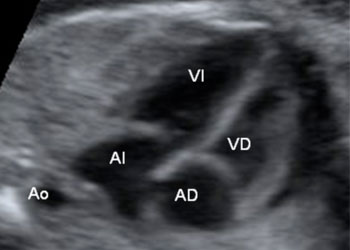

Ejemplos de ecografías del embarazo